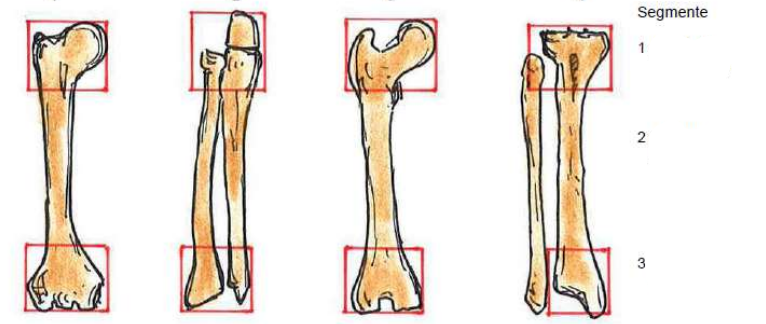

Klassifikation nach AO

1 Humerus - Oberarm

2 Ulna + Radius - Elle + Speiche

3 Femur - Oberschenkel

4 Tibia + Fibula - Schien- + Wadenbein

Klassifikation des Segmentes

1 proximal - körpernah

2 diaphysär - Schaftbereich

3 distal - körperfern

Klassifikation nach Frakturtyp: Schaftbereich

A: einfach

B: einfach Mehrfragment

C: komplexe Fraktur

Frakturtyp im Gelenkbereich

A: extraartikulär

B: artikulär partiell

C: artikulär vollständig